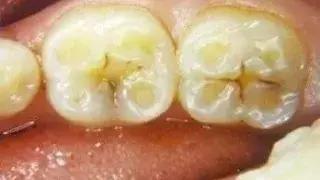

6、龋齿:龋齿又分为浅龋、中龋和深龋。初期浅龋只是釉质龋,并没有什么明显症状,大多只表现为牙齿表面出现脱矿,有白垩色或黄褐色、黑色斑块。到了中龋及深龋,龋坏就会发展到牙本质,此时就会出现牙齿敏感、酸痛,吃冷热刺激性食物时,会出现一过性刺激痛。对于此种原因,要及时进行腐质去除,然后补牙。